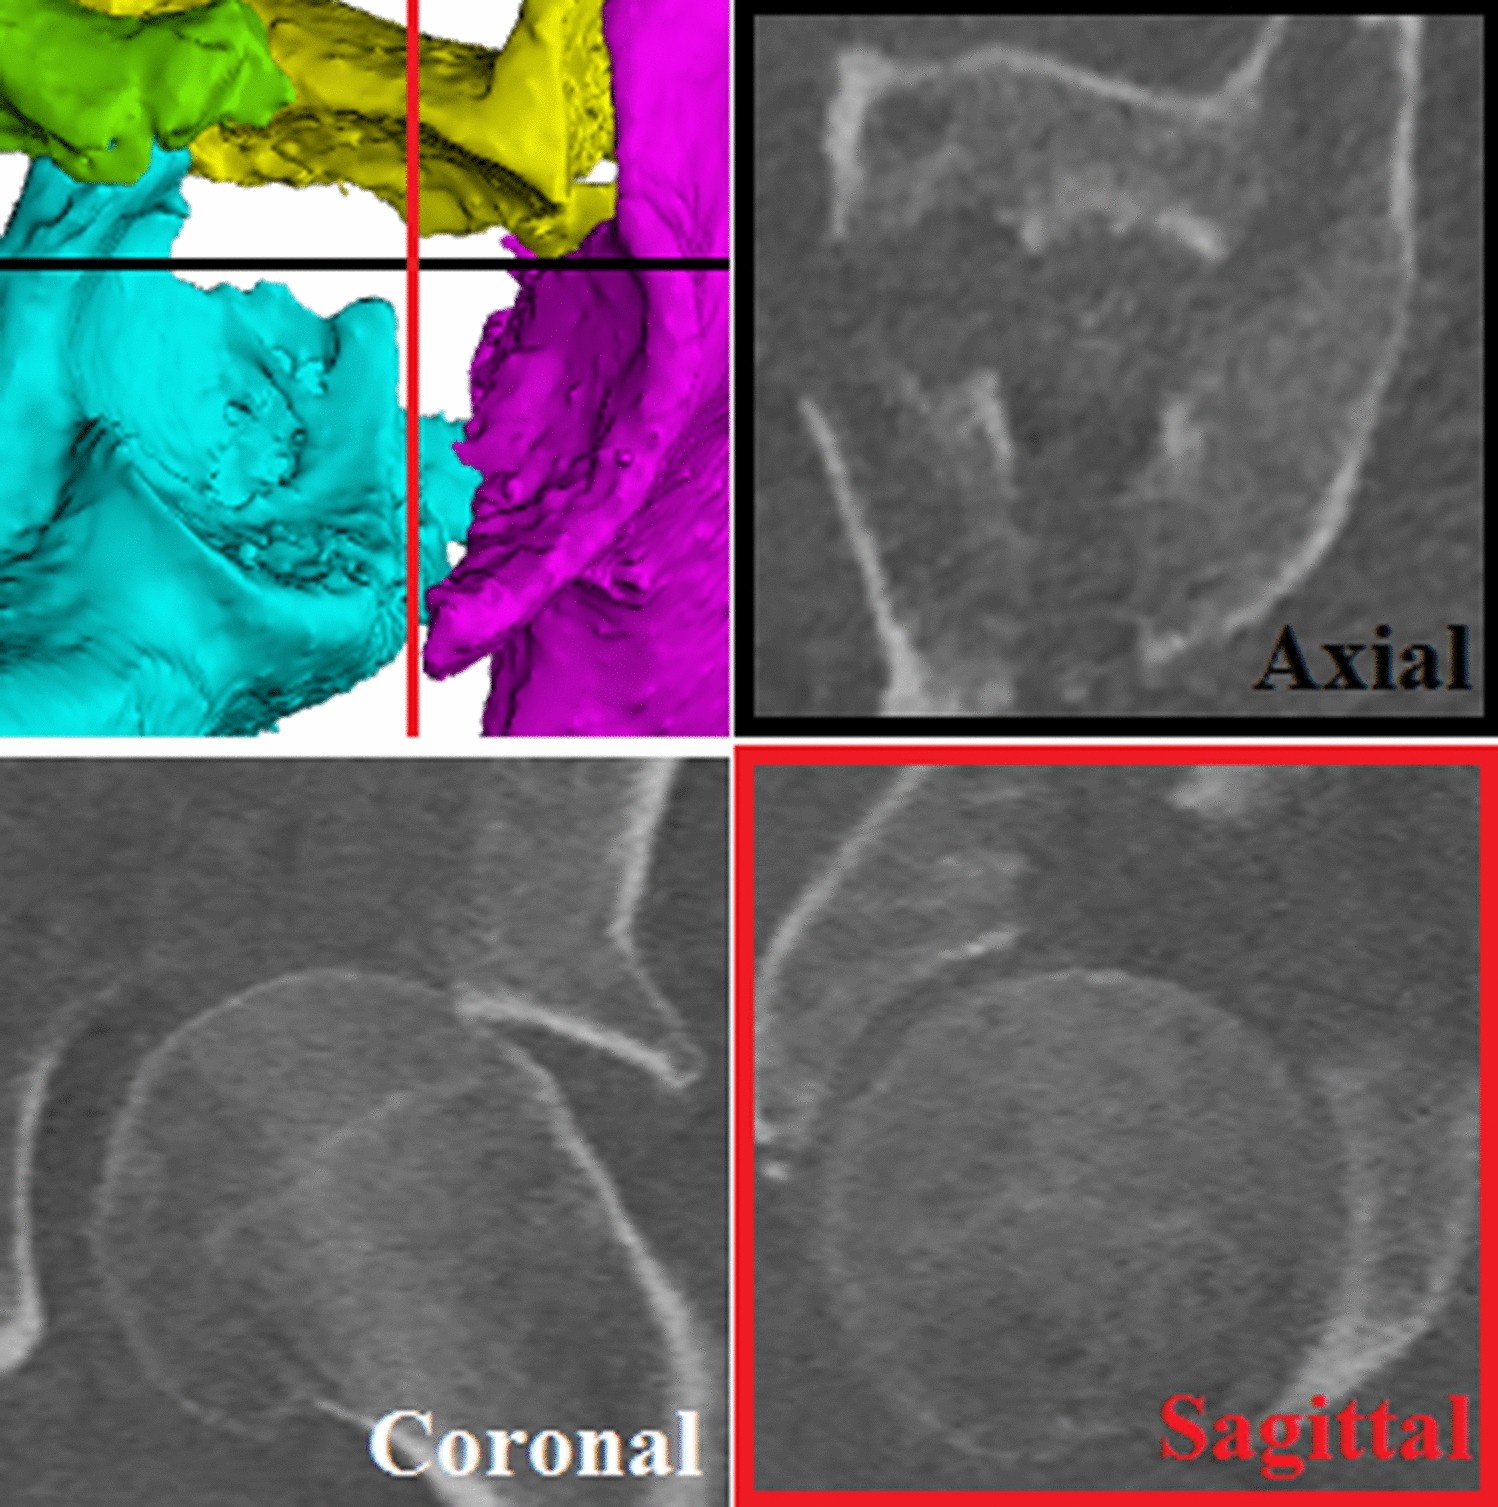

Figure 4

From: The accuracy of gap and step-off measurements in acetabular fracture treatment

A gap and step-off can be seen on a 3D view of the acetabulum (top left). The black line represents the axial plane and the red line represents the sagittal plane. Multiple fracture lines, with gaps and step-offs, can be seen on the CT slices.